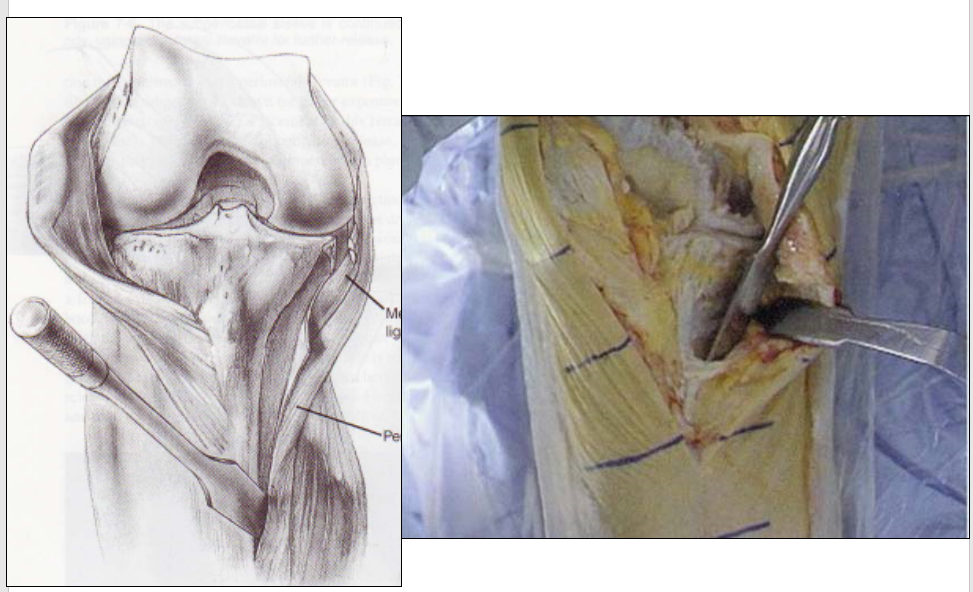

关键二、软组织平衡:伸直、屈曲对称的矩形间隙

先做伸直位平衡

松解内侧关节囊 MCL

截骨

切除内侧骨赘,内后角骨赘

平衡内外侧间隙

内侧副韧带缩紧术

内侧副韧带向远端拉紧

非吸收缝线,胫骨内侧切骨以远1cm处缝合,缩紧术后膝稳定支架3周

内侧副韧带推移术

骨膜分离内侧副韧带,鹅足腱,在屈膝10°位,适当内侧张力下内侧副韧带复合体下移,用韧带骑缝钉固定

术后制动3周,指导下进行屈伸训练